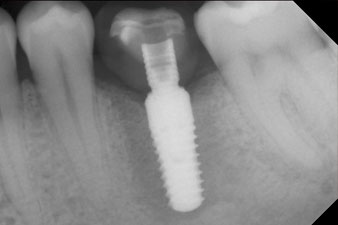

The final pictures show the screw-retained monolithic composite crown in place and the x-ray check (Fig. 9 and 10) (6).

Patients today expect quick treatment and thus determining the right time of restoration is becoming more and more important. To be able to estimate the micromovement for immediate restorations, the primary mechanically determined stability must be measured on the day of implantation. In contrast, to check that osseointegration was successful, the biologically determined secondary stability is measured. If implants are placed in soft bone, on average they tend to be more stable after uncovery than after placement (2). But if the implant is placed in hard or solid bone, as in the case study described here, the ISQ value remains constant or may even decrease if the initial values were high. The high mechanical stability is reduced by the osseointegration process and it is replaced by a biological anchorage.